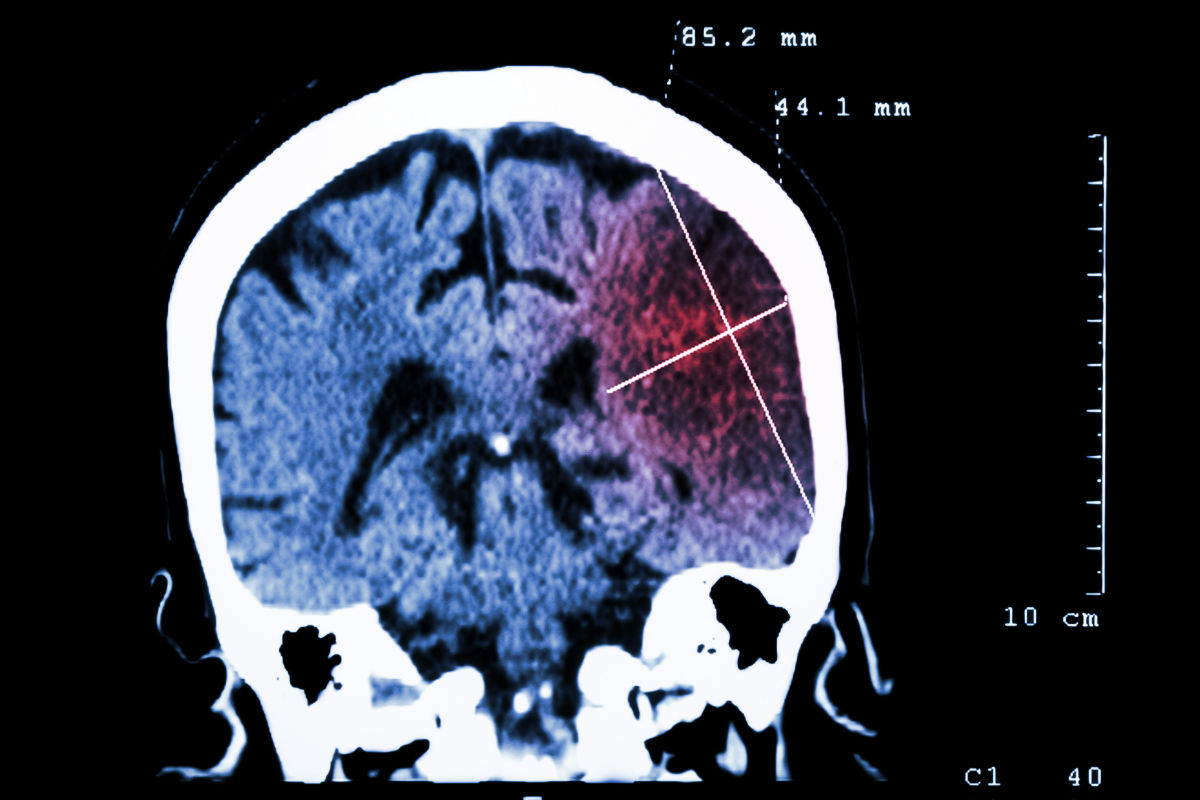

This minimally invasive surgical tool removes hematomas with low tissue disruption, protecting parts of your brain that control speech, memory and vision. The neurosurgeon is able to navigate between the natural folds in the brain and map the exact location of the tumor or blood clot using imaging. Then, through an opening no larger than a dime, the neurosurgeon can remove the clot or tumor from the deepest recesses of the brain without cutting or damaging anything else in its path.